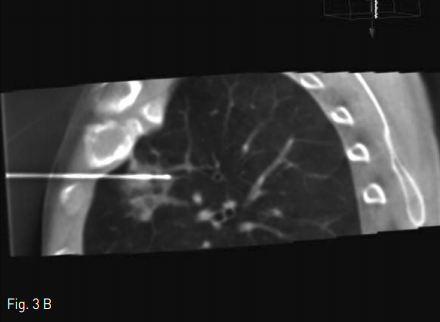

폐전이암 절제술 후 추적검사상 흉부 전산화 단층촬영에서 우측 폐 상엽에 0.7cm가량의 조영 증강되는 폐결절이 새롭게 관찰 되었다.(Fig. 1)

Fig 1A

Axial & coronal CT scan show a 0.7x0.5 cm sized enhancing solitary pulmonary nodule in right upper lobe.

Fig 1B